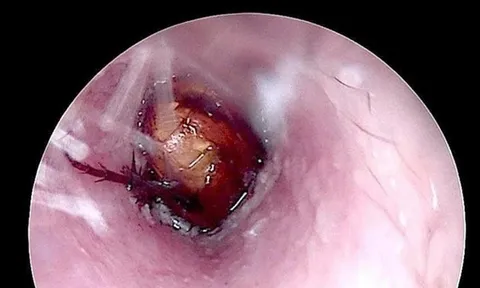

Ngoài ra, môi trường ẩm ướt còn khiến các bệnh da liễu như viêm da cơ địa, nấm da, chốc lở dễ bùng phát nếu vùng nếp gấp da không được vệ sinh và làm khô đúng cách.

Tình trạng ẩm ướt cũng dễ gây ra các bệnh lý da như nứt nẻ, viêm kẽ, nấm da hoặc viêm nang lông. Những vết trầy xước nhỏ nếu tiếp xúc với nước bẩn hoặc bùn đất có thể dẫn đến nhiễm trùng mô mềm nếu không được xử lý kịp thời.

Việc tự ý sử dụng thuốc, nhất là các loại thuốc bôi chứa corticoid khi chưa có chỉ định của bác sĩ, có thể làm nặng thêm tình trạng nhiễm trùng hoặc che lấp các triệu chứng quan trọng, gây khó khăn cho quá trình chẩn đoán và điều trị về sau.